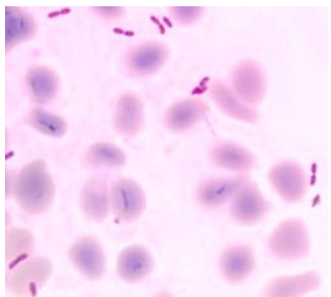

On day two, blood culture revealed Gram-negative bacilli with bipolar staining. MALDI-TOF analysis identified the organism as Burkholderia thailandensis, a rare and generally non-pathogenic relative of B. pseudomallei. Based on this result and the antibiogram, therapy was switched to oral levofloxacin, and the patient was discharged.

Given the persistent inflammatory syndrome, unusual neurological findings, and the rare organism initially isolated, the bacterial strain was reanalysed at a national reference laboratory. Multiplex PCR and additional testing confirmed Burkholderia pseudomallei.